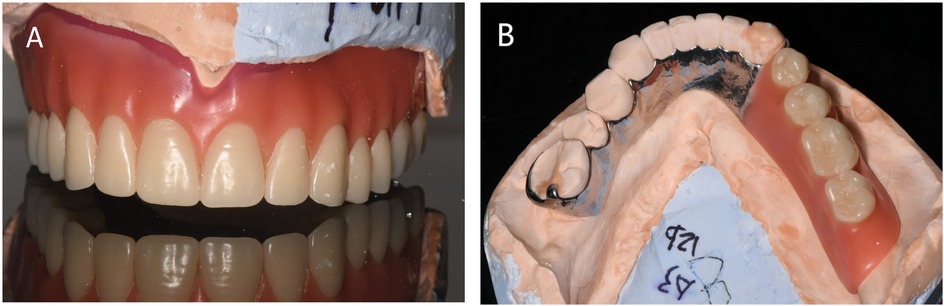

4. Trial of the denture wax pattern: The denture wax pattern (Figure 4) was used to verify the appropriate extension of the denture base margins, tenderness of the tissue surface, accuracy of the occlusal relationship, and whether the centric, protrusive, and lateral balanced occlusions were achieved. The patient's facial profile and vertical dimension were also assessed. To enhance the fit of the denture, an individual tray was fabricated using the maxillary wax pattern to record a closed functional impression (Figure 5), and the occlusal relationship was confirmed. A suction cup retainer ring was designed at the midpoint of the maxillary first molar, and the silicone rubber piece was fixed in the groove of the suction cup on the retainer ring.

Figure 4. Rendering of the denture wax type. (A) Buccal view of the wax-shaped maxillary denture. (B) mandibular denture.

Figure 6. Suction cup denture. (A) The front view of the maxillary denture. (B) The tissue surface of the maxillary denture.

Figure 7. Postoperative photographs. (A) Buccal view of denture. (B) Right-side occlusion (non-defect side). (C) Left-side occlusion (defect side). (D) Occlusal view of the maxillary denture. (E) Occlusal view of the mandibular denture.